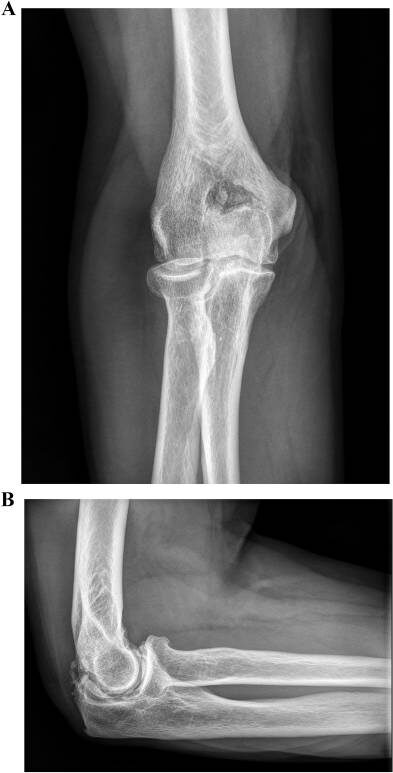

📌 рентгенография локтевого сустава - "золотой стандарт" диагностики остеоартрита;

Остеоартрит локтевого сустава